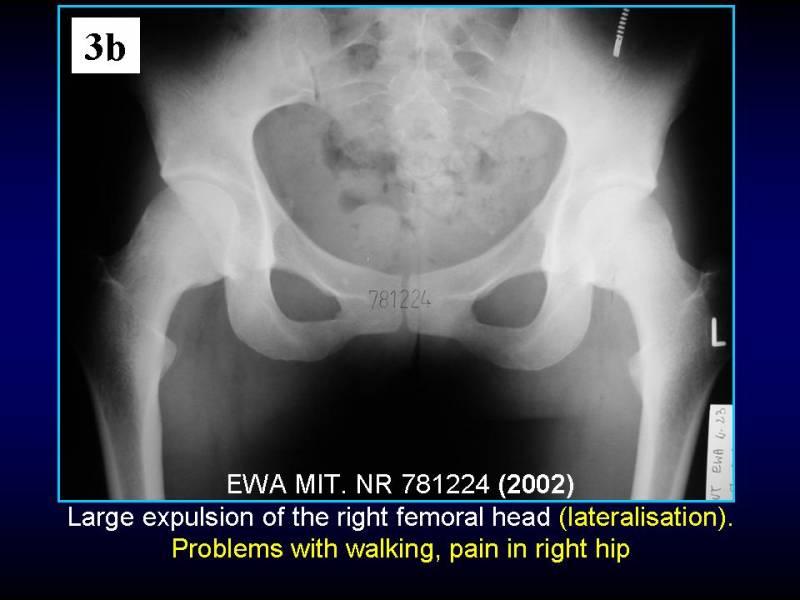

Wody geotermalne w ortopedii. Geothermal water in orthopaedic therapy.